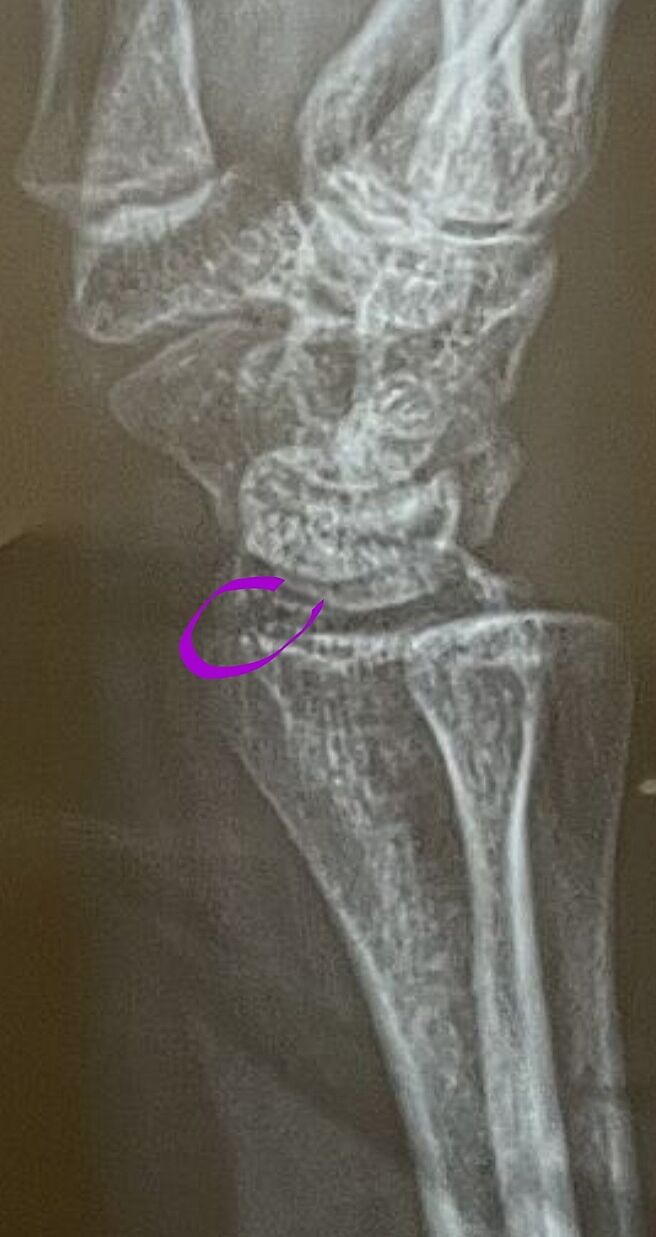

Хто розбирається у знімкках чи є перелом?

По діагнозу - перелом шилоподібного відростка правої променевої кістки

А можете обвести де саме? Бо є дві протилежні думки, а я не бачу де саме

Один лікар сказав, що перелом інший нічого не побачив

Я правда лікар акушер-гінеколог, але я не бачу перелому шилоподібного відростку

Возможно, что есть